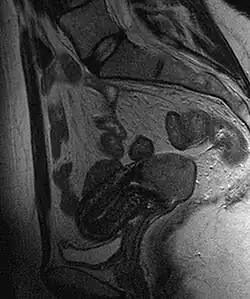

Cervical cancer seen on a T2-weighted sagittal MR image of the pelvis

This large squamous carcinoma (bottom of the picture) has obliterated the cervix and invaded the lower uterine segment. The uterus also has a round leiomyoma up higher.

Often, before the biopsy, the doctor asks for medical imaging to rule out other causes of a woman's symptoms. Imaging modalities such as ultrasound, CT scan, and MRI have been used to look for alternative disease, spread of the tumor, and effect on adjacent structures. Typically, they appear as heterogeneous masses on the cervix.[64]